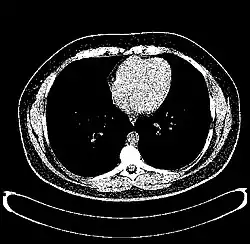

The Hounsfield scale (/ˈhaʊnzfiːld/ HOWNZ-feeld), named after Sir Godfrey Hounsfield, is a quantitative scale for describing radiodensity. It is frequently used in CT scans, where its value is also termed CT number.

| Parenchyma | Lung | −700 to −600[25] |